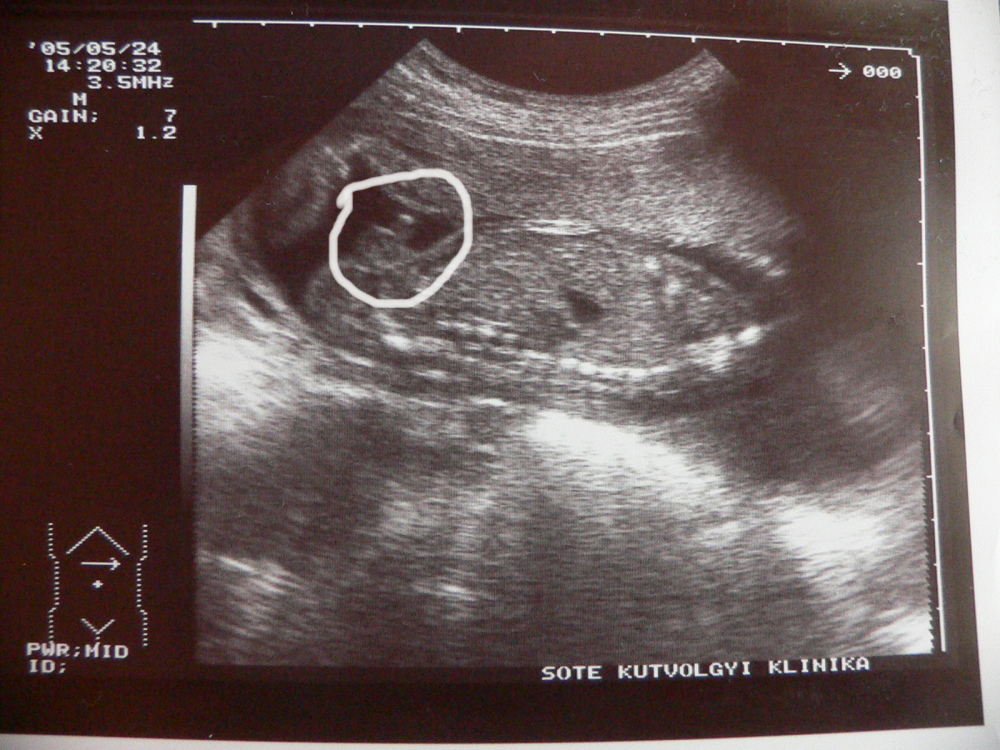

| 12. heti ultrahang. 6,5 cm.

láb, test, fej, kezek láthatóak. |